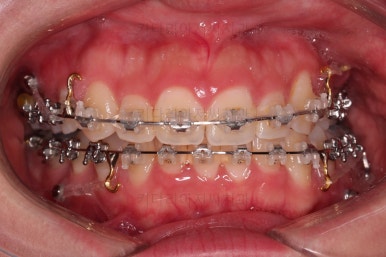

초진 시 입안의 모습입니다.

전반적으로 치열이 삐뚤고요.

위아래 중앙선이 약간 틀어져 있는데 많이 심한 편은 아니고요. 윗니가 배열된 U자 형태를 보면 아랫니보다 좁은 형태로 "악궁이 좁은" 상황이었습니다.

부산비대칭교정 마무리 때의 입안의 모습입니다.

가지런한 느낌은 좋지만 정중선 당연히 약간 안맞고요.

폭도 100%는 안맞아서 어금니쪽이 약간 애매한 교합이기도 했습니다.

하지만 이정도의 비대칭 상황에서 이정도의 교합은 교정만으로 할 수 있는 베스트가 아닌가 생각됩니다.